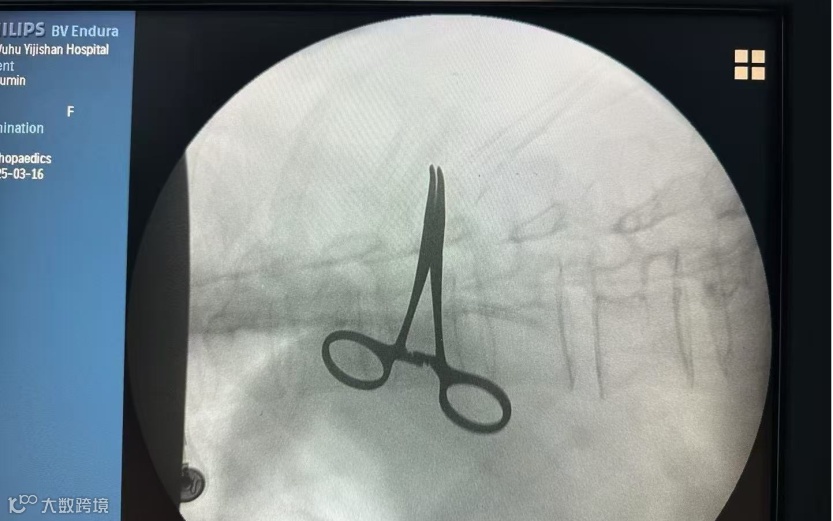

1、利用食道超声、脑氧检测技术与多个临床科室密切协作,开展疑难心脏手术、肝脏手术的术中监测和评估,大大降低了围术期并发症和死亡率的发生。